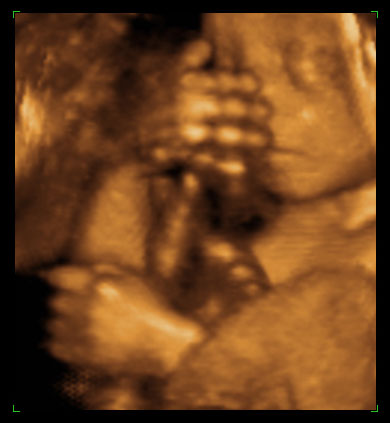

“A precise dose of anesthetic had put both the mother and the 24 week old fetus safely and limply to sleep. And now, lifting the little arm gently to rotate the 1 pound body into position, pediatric surgeon Michael Harrison poised his scalpel just under the rib cage. This astonishing intrusion on an unborn life took place on June 15, 1989; it was necessary because this tiny patient’s diaphragm had failed to close as it should have.”

Surgeons can now perform delicate surgery in the womb. However, babies at 24 weeks can be aborted in any state in the United States.

See pictures of babies aborted at 24 weeks.